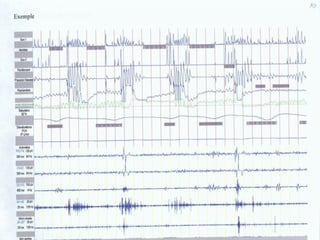

Polysomnographie

 EEG

 EMG

 EOG

 Flux respiratoire

 Mouvements respiratoires

 Oxymétrie

 ECG

 Position

 T.A.

 Pression œsophagienne

 EMG jambiers

Polysomnographie  EEG  EMG EOG  Flux respiratoire  Mouvements respiratoires  Oxymétrie  ECG  Position  T.A.  Pression œsophagienne  EMG jambiers